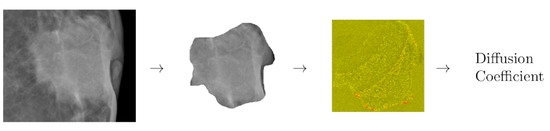

2. MDC Calculation

2.1. Building the Simulation Space from Mammograms

3. Results

| Before | |||

| After | |||